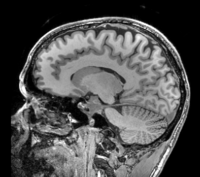

v3.6.1 Slicer3-6Announcement-v1.png Slicer Registration Library Case #11:

Co-registration of two anatomic brain atlases for merging of structure labels

This is an example of inter-subject registration via surface matching. The structures of interest are a small subset of the entire image, hence registration is not driven by image intensities but rather two model surfaces derived from the labelmaps.

MRI, brain, head, inter-subject, atlas to atlas, surface-based registration, thalamic nuclei

Registration Results

unregistered

after ICP Surface Registration + Clipping